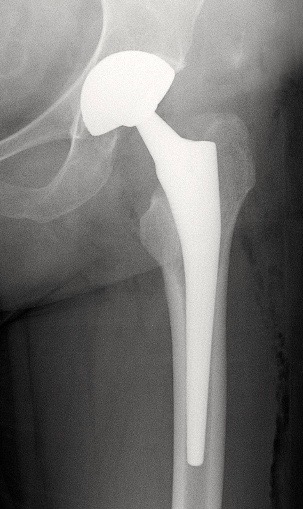

A. PTH avec double mobilité